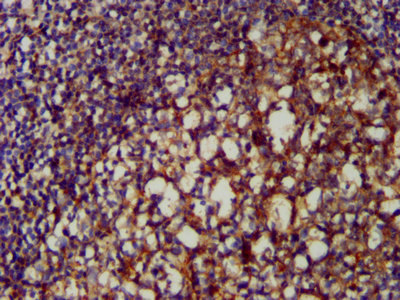

IHC image of CSB-PA06029A0Rb diluted at 1:200 and staining in paraffin-embedded human tonsil tissue performed on a Leica BondTM system. After dewaxing and hydration, antigen retrieval was mediated by high pressure in a citrate buffer (pH 6.0). Section was blocked with 10% normal goat serum 30min at RT. Then primary antibody (1% BSA) was incubated at 4°C overnight. The primary is detected by a biotinylated secondary antibody and visualized using an HRP conjugated SP system.